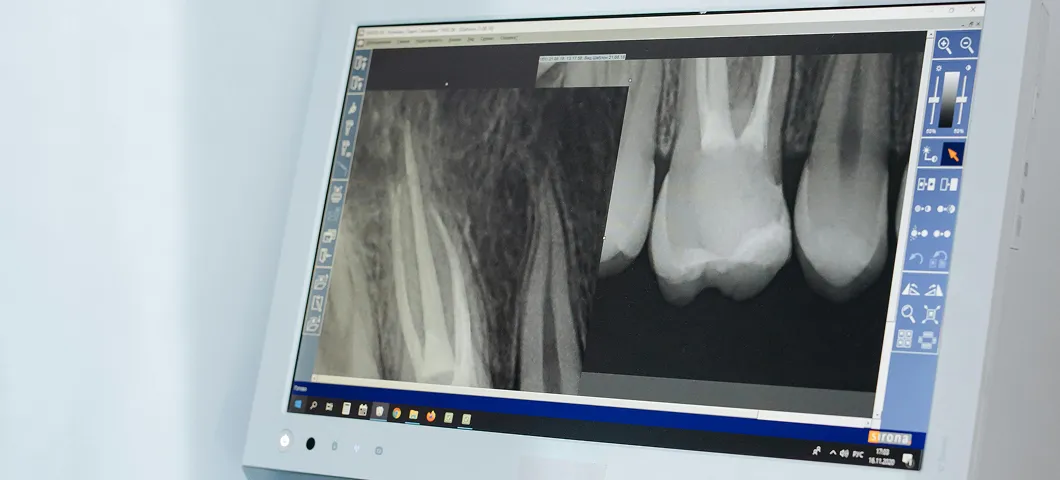

Save Your Natural Tooth

A severe toothache from an infection can feel debilitating. Luckily, root canal therapy is a gentle way to relieve your pain and, most importantly, save your natural tooth from needing to be extracted.